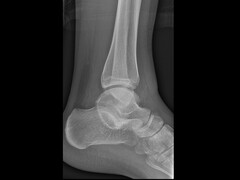

De hielkieptest Ter aanvulling een anekdote waarmee de tarsale coalitie wat toegankelijker is voor de eerstelijns diagnostiek. Wekenlang heb ik rondgelopen met een calcaneus en een talus in de diepe zak van mijn witte jas. Allebei echt en beide van rechts…